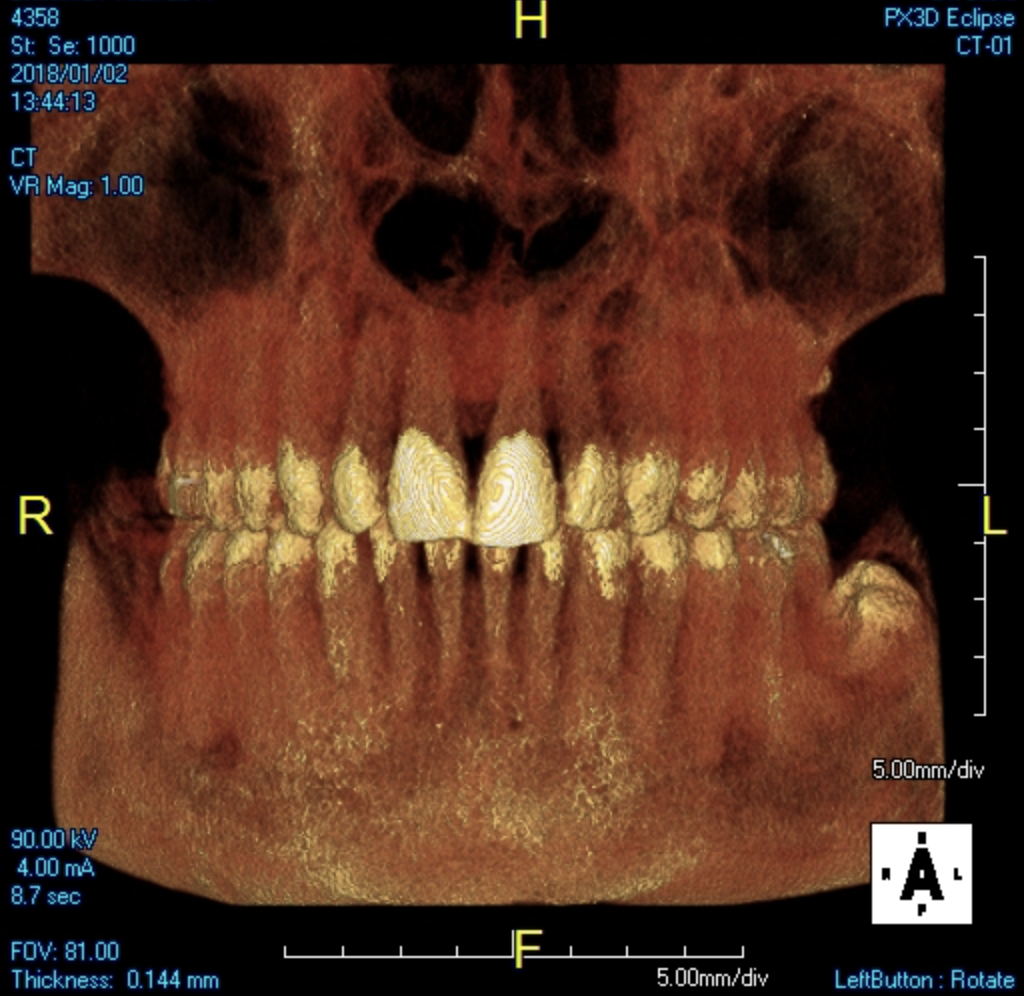

A young man presented with a fractured maxillary left-central incisor on a Monday morning after a Saturday evening discussion that did not end well (Figure 1). Visual oral examination and palpation of the structures revealed mobility of 3+, pain on palpation and percussion, a thick soft-tissue profile, and a low lip line. Gingival zeniths were irregular, there was a class II division 2 deep bite, and the periodontium was healthy overall (Figure 2 through Figure 4). Radiographs requested at the time of the initial visit were periapicals, panoramic, and CBCT images (Figure 5 and Figure 6). After all images and information were reviewed and the extent of his injury was discussed, the patient was presented with the following options: removable prosthetics, fixed partial denture, extract and do nothing, or extract and place a dental implant with bone augmentation.

Reviewing the CBCT images with the patient proved beneficial because he was able to clearly see the complete fracture of his tooth in the apical third of the root (Figure 6). Figure 5 represented what is a common radiograph in most dental offices, but it was not clear enough to diagnose a root fracture of this nature. The patient understood that the prognosis was poor and that the long-term restoration he wanted would mimic nature and be maintainable like natural dentition. The visual examination and photographs provided a basis for subsequent dental therapy and a definitive treatment plan for the future. The patient decided to move forward with tooth extraction, grafting, and immediate dental-implant placement with a screw-retained provisional out of occlusion.

Fig 1. CBCT image (preoperative).

Figure 1